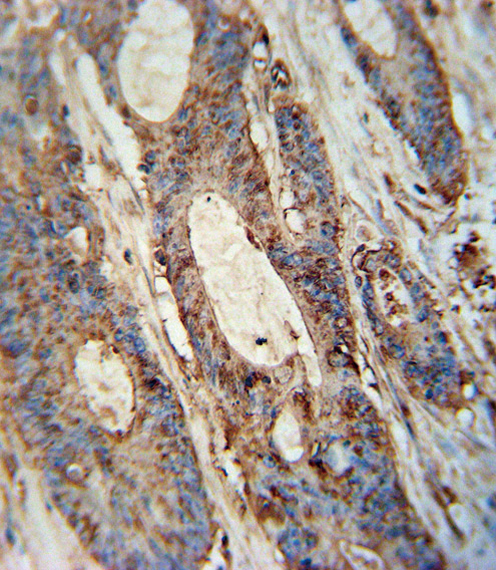

FAM46A antibody (Center) (Cat. APR03441G) immunohistochemistry analysis in formalin fixed and paraffin embedded human colon carcinoma followed by peroxidase conjugation of the secondary antibody and DAB staining. This data demonstrates the use of the FAM46A antibody (Center) for immunohistochemistry. Clinical relevance has not been evaluated. |